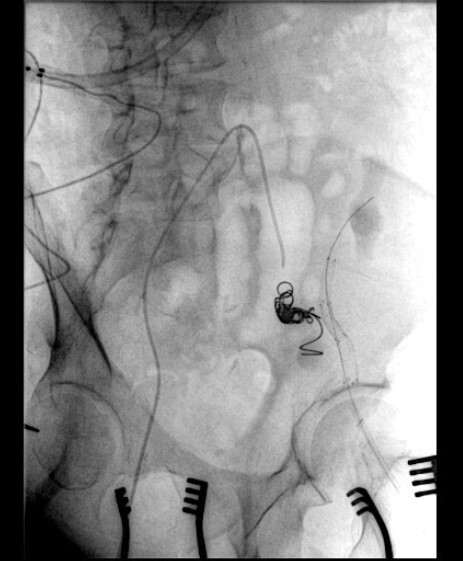

The intervention successfully isolated the pseudoaneurysm and preserved graft function. Post-procedure, the patient's serum creatinine levels improved from 4.8 mg/dL to 1.9 mg/dL at one week and stabilized at 2.3 mg/dL at the 6-month follow-up. Imaging confirmed no residual flow in the aneurysm (Figure 2), and no vascular complications were observed during the follow-up period.